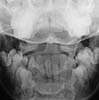

Adolescent. RTA knockdown. ATLS protocols. Put in hard collar. These films below obtained. no neck pain, no swelling, no neurology, no dysaethesia, no previous neck trauma. Closed # tibia.

Lateral

Odontoid

With the lack of symmetry in the AP, I guess you did a CT or MR. Can we see it?

I cannot make a diagnosis from these films (which are clearly reproduced, I cannot decipher the information). There is a bony ossicle (?fx fragment) posteriorly between O-C1 and asymmetry of the atlas on open mouth odontoid. I would keep her neck braced and follow the clinical exam; probably with additional studies of the O-C1junction (CT +-MRI) and review with radiologist.

MRI was unremarkable except for showing the bony ossicle. Radiologists said the peg view was rotated.

Our radiologists tell me its part of a congenital arch. I have never seen this kind of remnant at this level. Has anyone else?